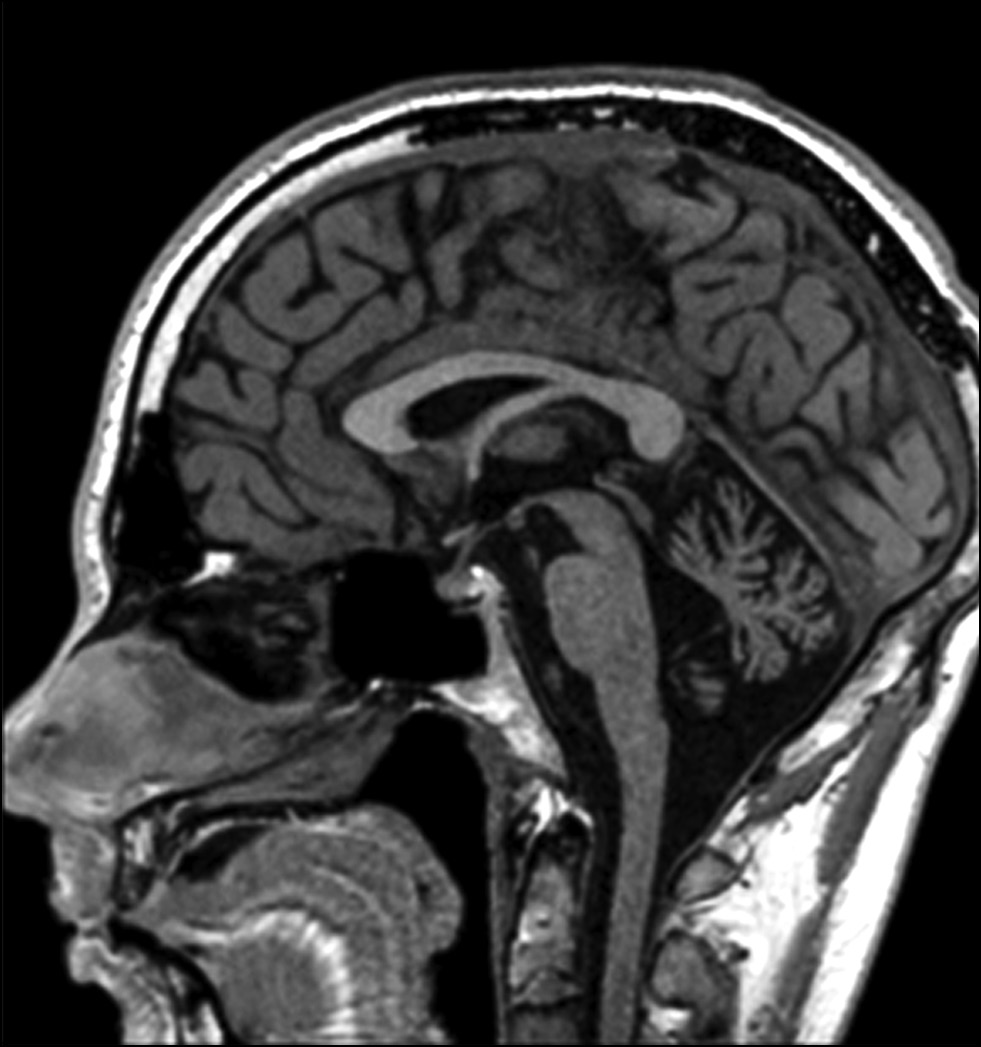

При МРТ головного мозга у 42% изменений обнаружено не было. У 6 (50%) пациентов выявлены признаки атрофии мозжечка от легкой до умеренной степени: атрофия червя мозжечка (n = 3), диффузная атрофия мозжечка (n = 2), гемиатрофия полушария мозжечка (n = 1) (рис. 2). В одном случае (пациентка #19) наблюдались Т2/T2-FLAIR-гиперинтенсивные изменения от медиальных отделов височных долей и структур мозжечка с признаками патологического накопления контрастного вещества на постконтрастных Т1 (Т1-С+) взвешенных изображениях (рис. 3). Примечательно, что, несмотря на МРТ-данные о вовлечении височных долей, клиническая картина заболевания была представлена МА и лишь легким когнитивным дефицитом (MoCA — 24 балла). С учетом нетипичной МРТ-картины пациентке проводился обширный онкологический поиск — патологии не обнаружено.

Рис. 2. МРТ головного мозга пациентки #28: Т2-FLAIR, сагитальный срез — атрофия червя мозжечка